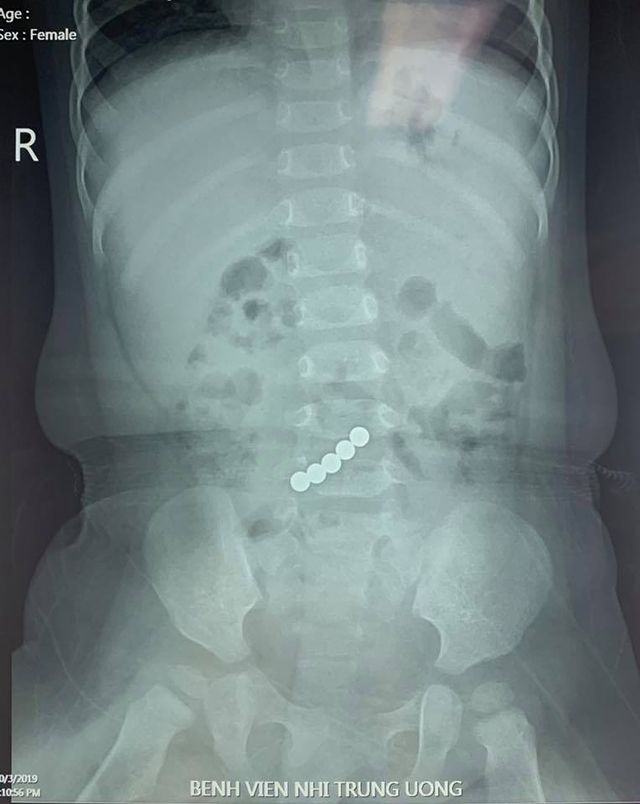

Ngay khi phát hiện con nuốt phải dị vật. Gia đình đã đưa ngay bé đến Bệnh viện Nhi Trung ương cấp cứu. Hình ảnh chụp X-Quang cho thấy những viên nam châm xếp hình trong ruột của bé gái.

5 viên nam châm xếp hình nằm thành một đường thẳng trong ruột bé gái 1 tuổi khiến bé bị thủng ruột. Tai nạn xảy ra khi bé gái này đang chơi cùng một bé hàng xóm 5 tuổi, cô bé thấy tò mò với những viên nam châm xếp hình nhỏ sắc màu nên cho vào miệng nuốt.